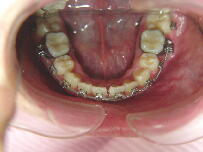

症例2 (20代 女性) 非抜歯例 ![]() ![]() ![]()

初診時平成12年6月